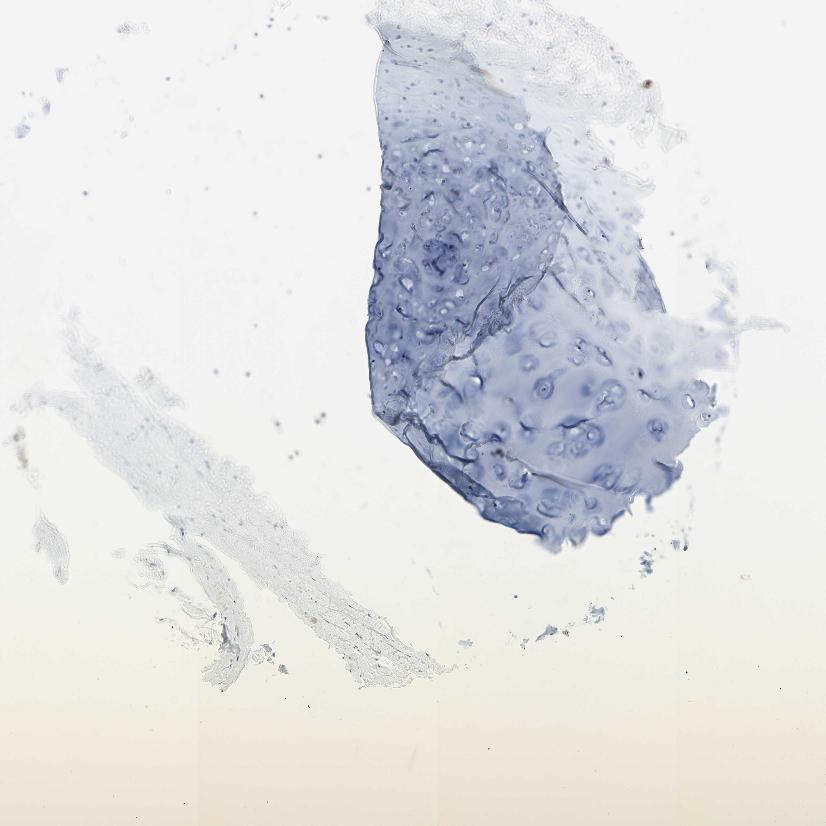

SOFT TISSUE 1 - Antibody stainingi

Antibody staining in the annotated cell types in the current human tissue is reported as not detected, low, medium, or high, based on conventional immunohistochemistry profiling in selected tissues. This score is based on the combination of the staining intensity and fraction of stained cells.

Each image is clickable and will lead to virtual microscopy that enables deeper exploration of all samples and also displays staining intensity scores, fraction scores and subcellular localization as well as patient and tissue information for each sample.

Antibody HPA006154Antibody HPA012012Antibody CAB009454

Chondrocytes --Not detected

Fibroblasts Not detectedNot detectedNot detected

Peripheral nerve Not detected-Not detected